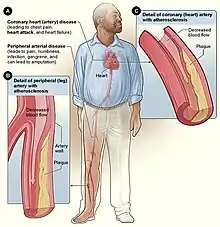

Cardiovascular disease

Inhalation of tobacco smoke causes several immediate responses within the heart and blood vessels. Within one minute the heart rate begins to rise, increasing by as much as 30 percent during the first 10 minutes of smoking. Carbon monoxide in tobacco smoke exerts negative effects by reducing the blood's ability to carry oxygen.[92]

Smoking also increases the chance of heart disease, stroke, atherosclerosis, and peripheral vascular disease.[93][94] Several ingredients of tobacco lead to the narrowing of blood vessels, increasing the likelihood of a blockage, and thus a heart attack or stroke. According to a study by an international team of researchers, people under 40 are five times more likely to have a heart attack if they are smokers.[95][96]

Smoking also tends to increase blood cholesterol levels. Furthermore, the ratio of high-density lipoprotein (HDL, also known as the "good" cholesterol) to low-density lipoprotein (LDL, also known as the "bad" cholesterol) tends to be lower in smokers compared to non-smokers. Smoking also raises the levels of fibrinogen and increases platelet production (both involved in blood clotting) which makes the blood thicker and more likely to clot. Carbon monoxide binds to hemoglobin (the oxygen-carrying component in red blood cells), resulting in a much stabler complex than hemoglobin bound with oxygen or carbon dioxide—the result is permanent loss of blood cell functionality. Blood cells are naturally recycled after a certain period of time, allowing for the creation of new, functional red blood cells. However, if carbon monoxide exposure reaches a certain point before they can be recycled, hypoxia (and later death) occurs. All these factors make smokers more at risk of developing various forms of arteriosclerosis (hardening of the arteries). As the arteriosclerosis progresses, blood flows less easily through rigid and narrowed blood vessels, making the blood more likely to form a thrombosis (clot). Sudden blockage of a blood vessel may lead to an infarction (stroke or heart attack). However, the effects of smoking on the heart may be more subtle. These conditions may develop gradually given the smoking-healing cycle (the human body heals itself between periods of smoking), and therefore a smoker may develop less significant disorders such as worsening or maintenance of unpleasant dermatological conditions, e.g. eczema, due to reduced blood supply. Smoking also increases blood pressure and weakens blood vessels.[103]